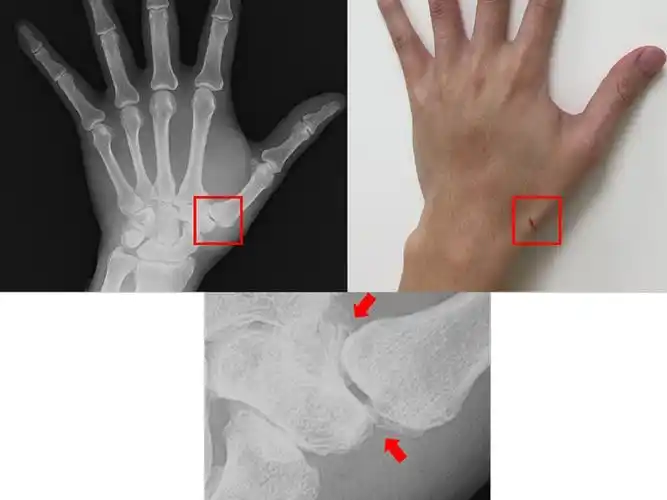

经x光摄影发觉拇指腕掌关节退化并骨刺增生的情形(图片/台大竹东分院

微创治疗儿童掌骨头骨折